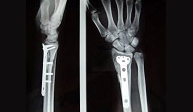

Las fracturas del radio distal son las más frecuentes de la extremidad superior. En gente joven se asocian a traumatismos de alta energía como accidentes de tráfico, caídas desde altura o accidentes deportivos. En el anciano lacarencia de hueso a este nivel (osteoporosis) hace de esta región un lugar muy susceptible de fractura con pequeños impactos.

El paciente de edad se beneficia habitualmente del tratamiento conservador con escayola. En el paciente joven el desplazamiento suele ser difícilmente manejable con inmovilización con yeso por lo que es frecuente la realización de una pequeñaintervención para la recuperación anatómica de la muñeca pudiendo reincorporarse a su actividad habitual en el menor tiempo posible y con el menor riesgo de complicaciones.